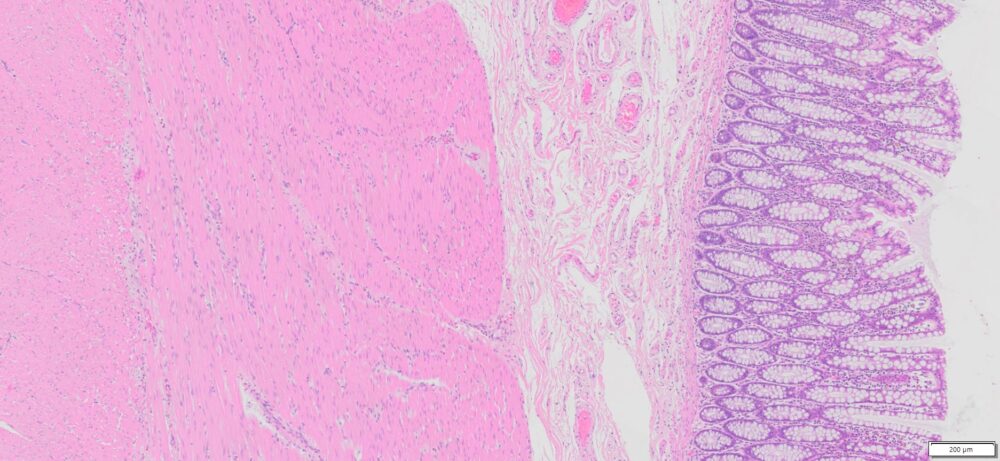

Description

| SKU# | Organ | Pathology Diagnosis | Gender | Age | Grade | TMN | Thickness | IHC Data |

| HuPS-07004A | Human Colon | Normal colon tissue | Male | 71 | — | — | 5μm |

More Image